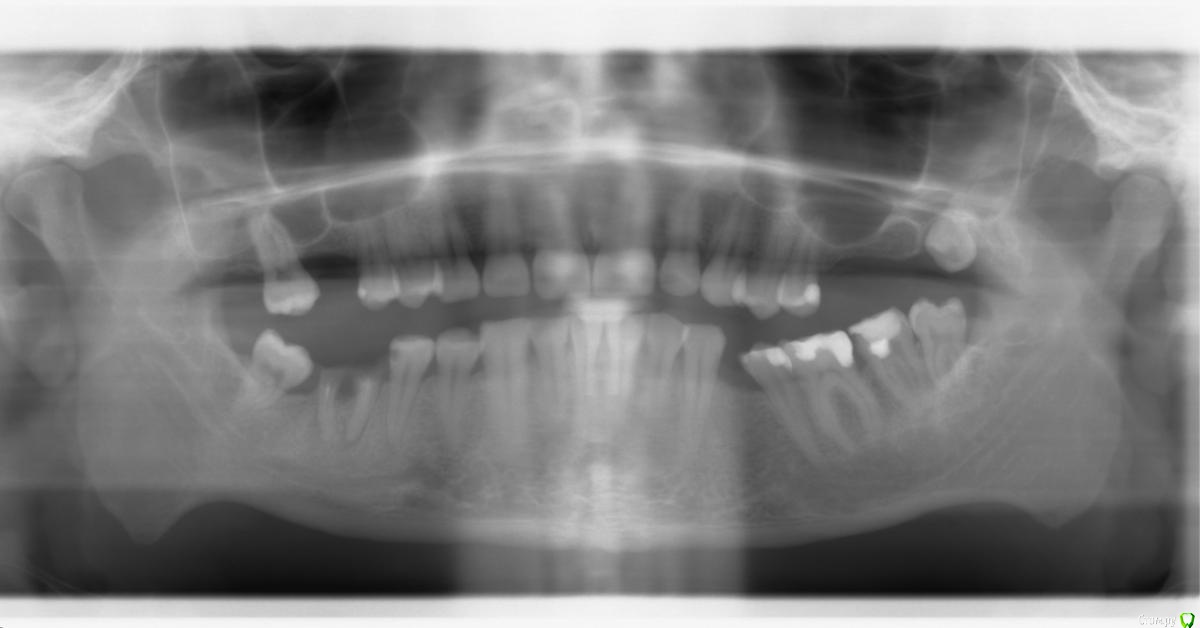

Andrei86 Опубликовано 12 сентября, 2017 Поделиться Опубликовано 12 сентября, 2017 (изменено) Здравстуйте, Кратко опишу ситуацию. Более 5 лет на удалял много зубов, сейчас хочу привести челюсть в порядок.Удалил, нижние:с право: 6,8с лево: 4верхние, с право: 6,8с лево:6,7 а так же 8-ка не вылезла до конца. 1) Из за того что с верху довольно долго нет 6,7 и считай что 8-ки , то нижние вылезли до верхней десны, то есть место для имплантов нет. 2) На сколько я понял нет костного объема.3) Гайморовые пазухи очень близко к верхним зубам (посмотрел на снимок и вообще в шоке, там не то что близко... но я в этом деле вообще мало что понимаю) Подскажите пожалуйста с чего вообще начать? Я понимаю, что начать надо с похода к врачу. Дело в том, живу в стране где с этим совсем плохо - во первых дорого, во вторых нет нормальных специалистов, вроде как есть но что-то они косячат слишком часто.Вообщем хочу запланировать отпуска и поехать в Россию/Украину/Белоруссию и привести всё в порядок, на сколько это возможно.Скажите пожалуйста реально ли что-то сделать и на сколько все запущено? с чего начать?как "отодвинут" нижние зубы назад, что-бы было место на верх поставить импланты? синус лифтинг вообще возможен если так близко гаймаровые пазухи?Хочется собрать побольше информации от незаинтересованных профессионалов перед тем как обращусь к доктору который меня будет лечить. ПС. нумерация зубов не знаю на сколько правильная, посмотрел в инете (но по снимку наверное будет понятно)ПСС. Русский язык не родной. Большое спасибо за любую информацию. Изменено 12 сентября, 2017 пользователем Andrei86 Ссылка на комментарий

Andrei86 Опубликовано 13 сентября, 2017 Автор Поделиться Опубликовано 13 сентября, 2017 хорошо,постараюсь сделать на днях. А по этому можно что-то сказать? Ссылка на комментарий

red_butler Опубликовано 13 сентября, 2017 Поделиться Опубликовано 13 сентября, 2017 хорошо,постараюсь сделать на днях. А по этому можно что-то сказать?на верхней челюсти потребуется синуслифтинг. На нижней ортодонтическая подготовка. 1 Ссылка на комментарий